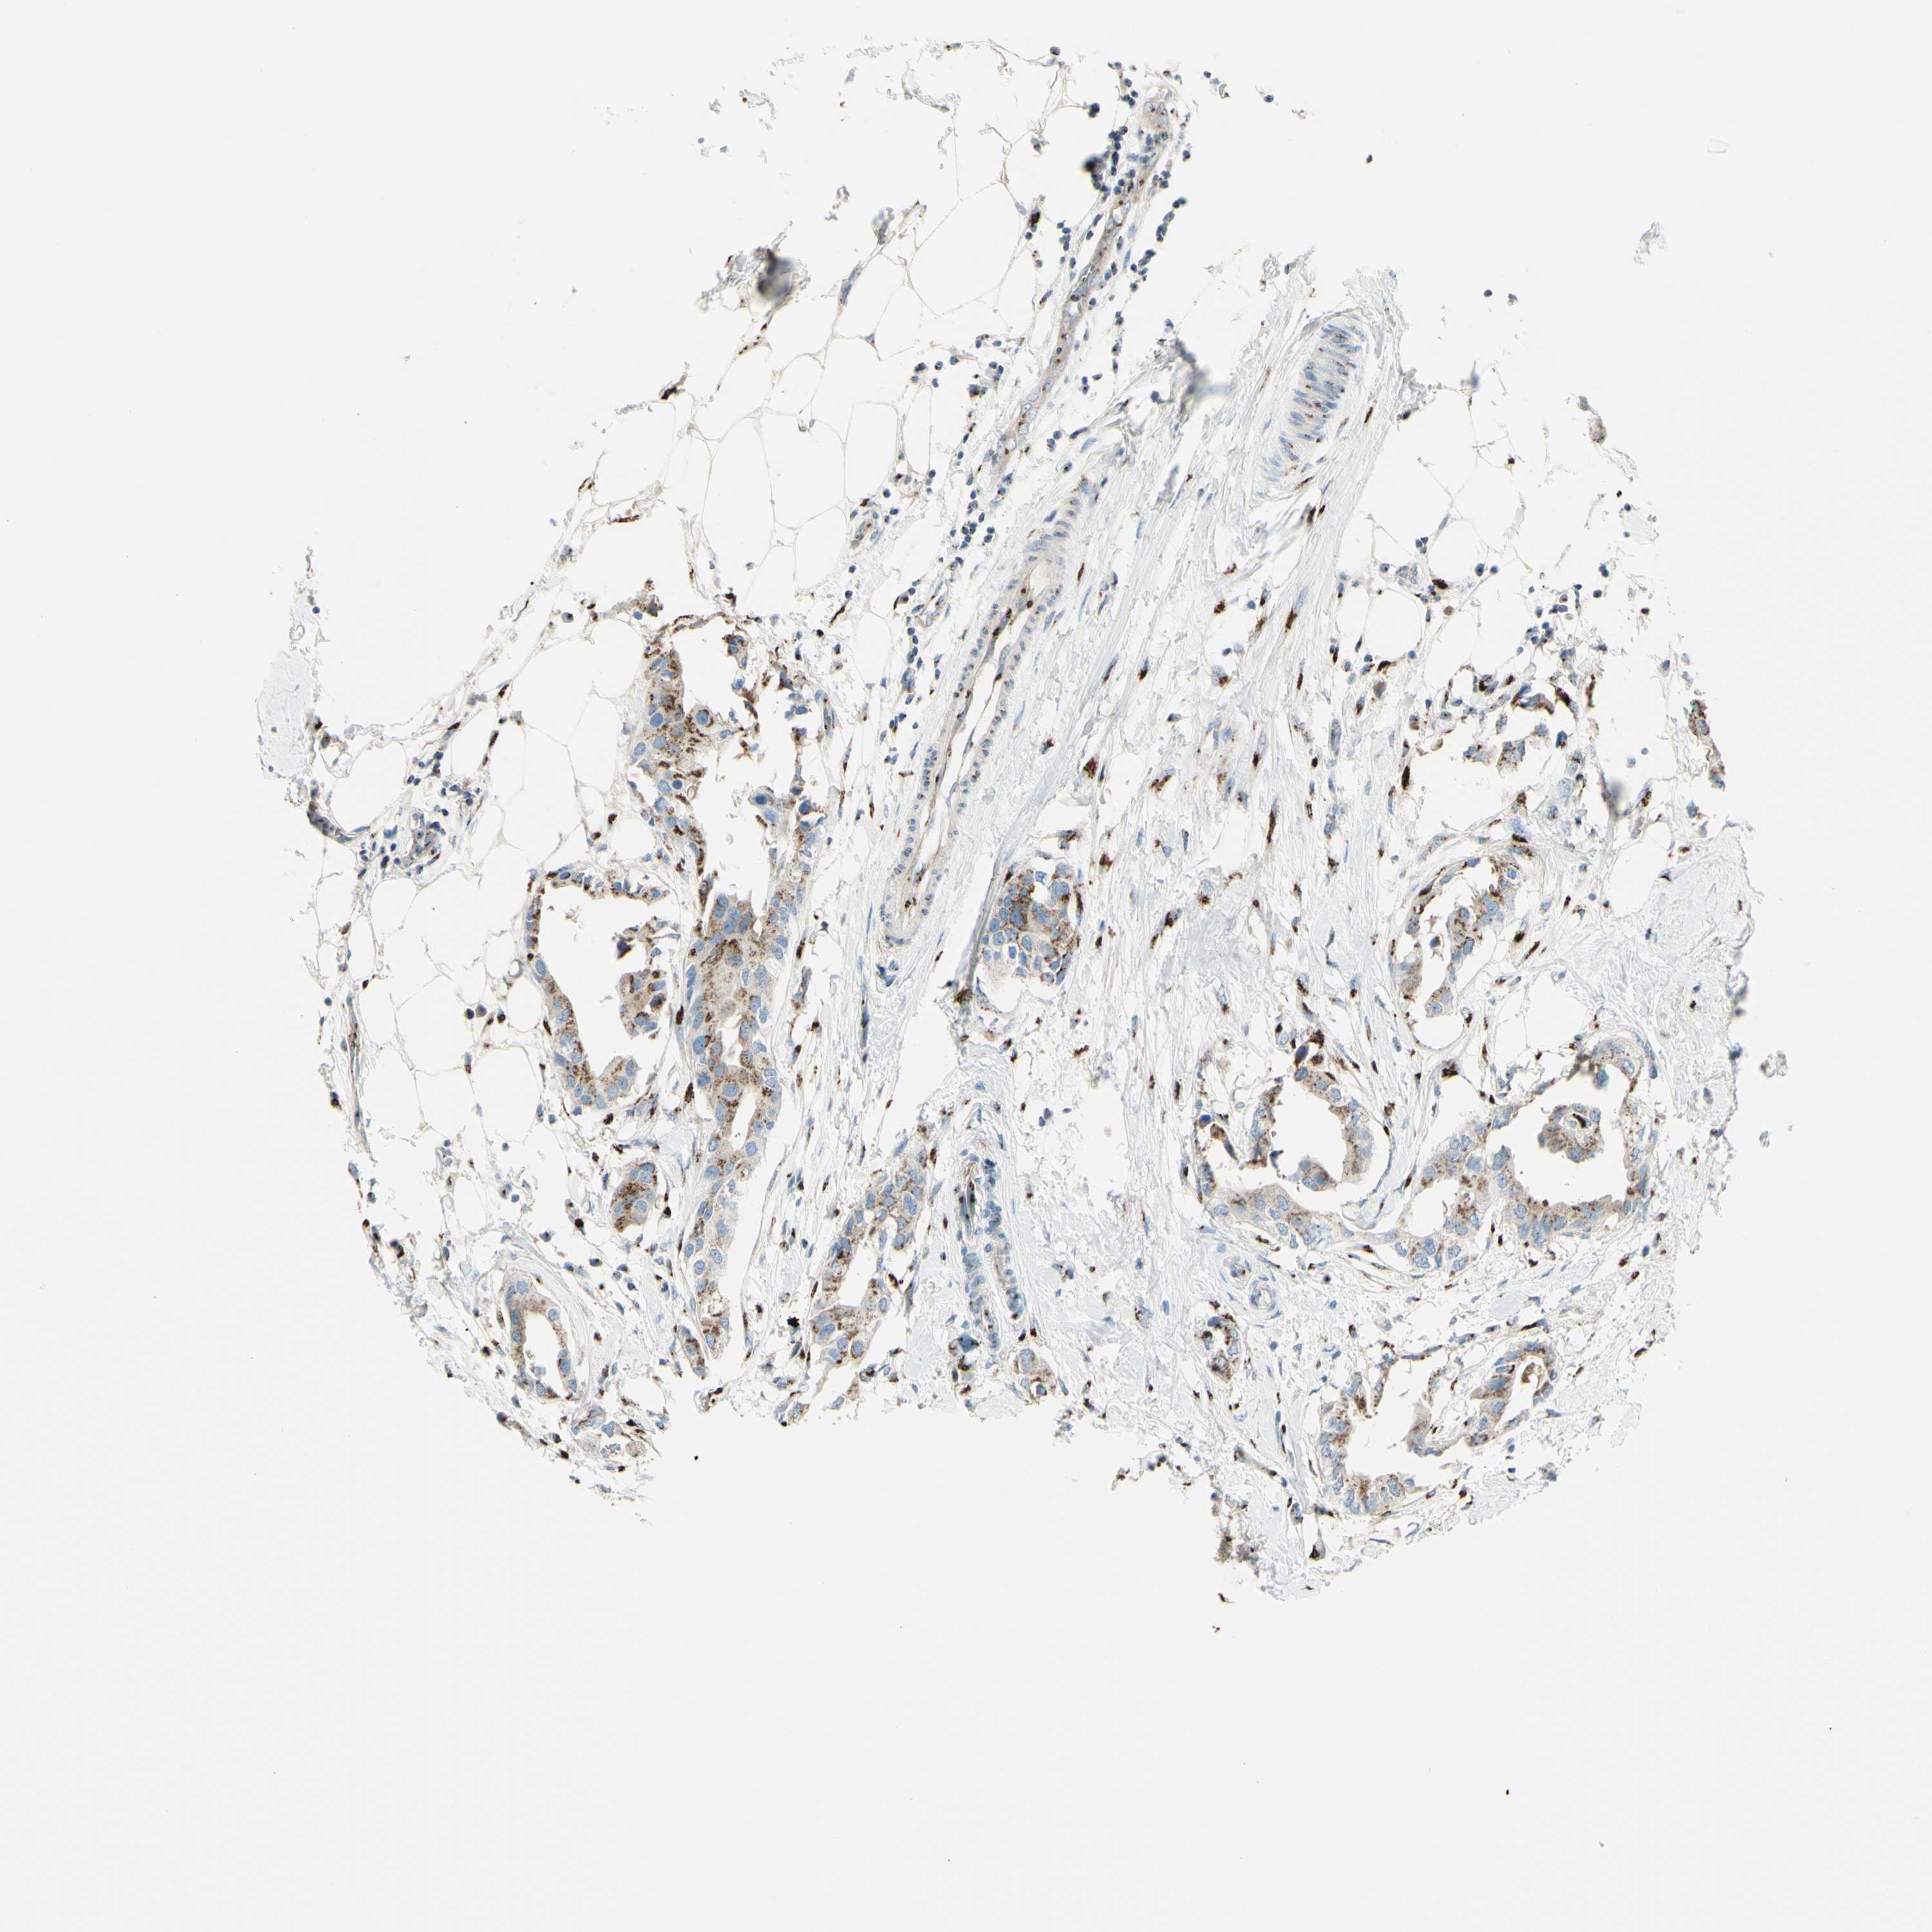

BRCA TCGA BRCA VALIDATION PROTEIN EXPRESSION

Breast cancer

Human cancer